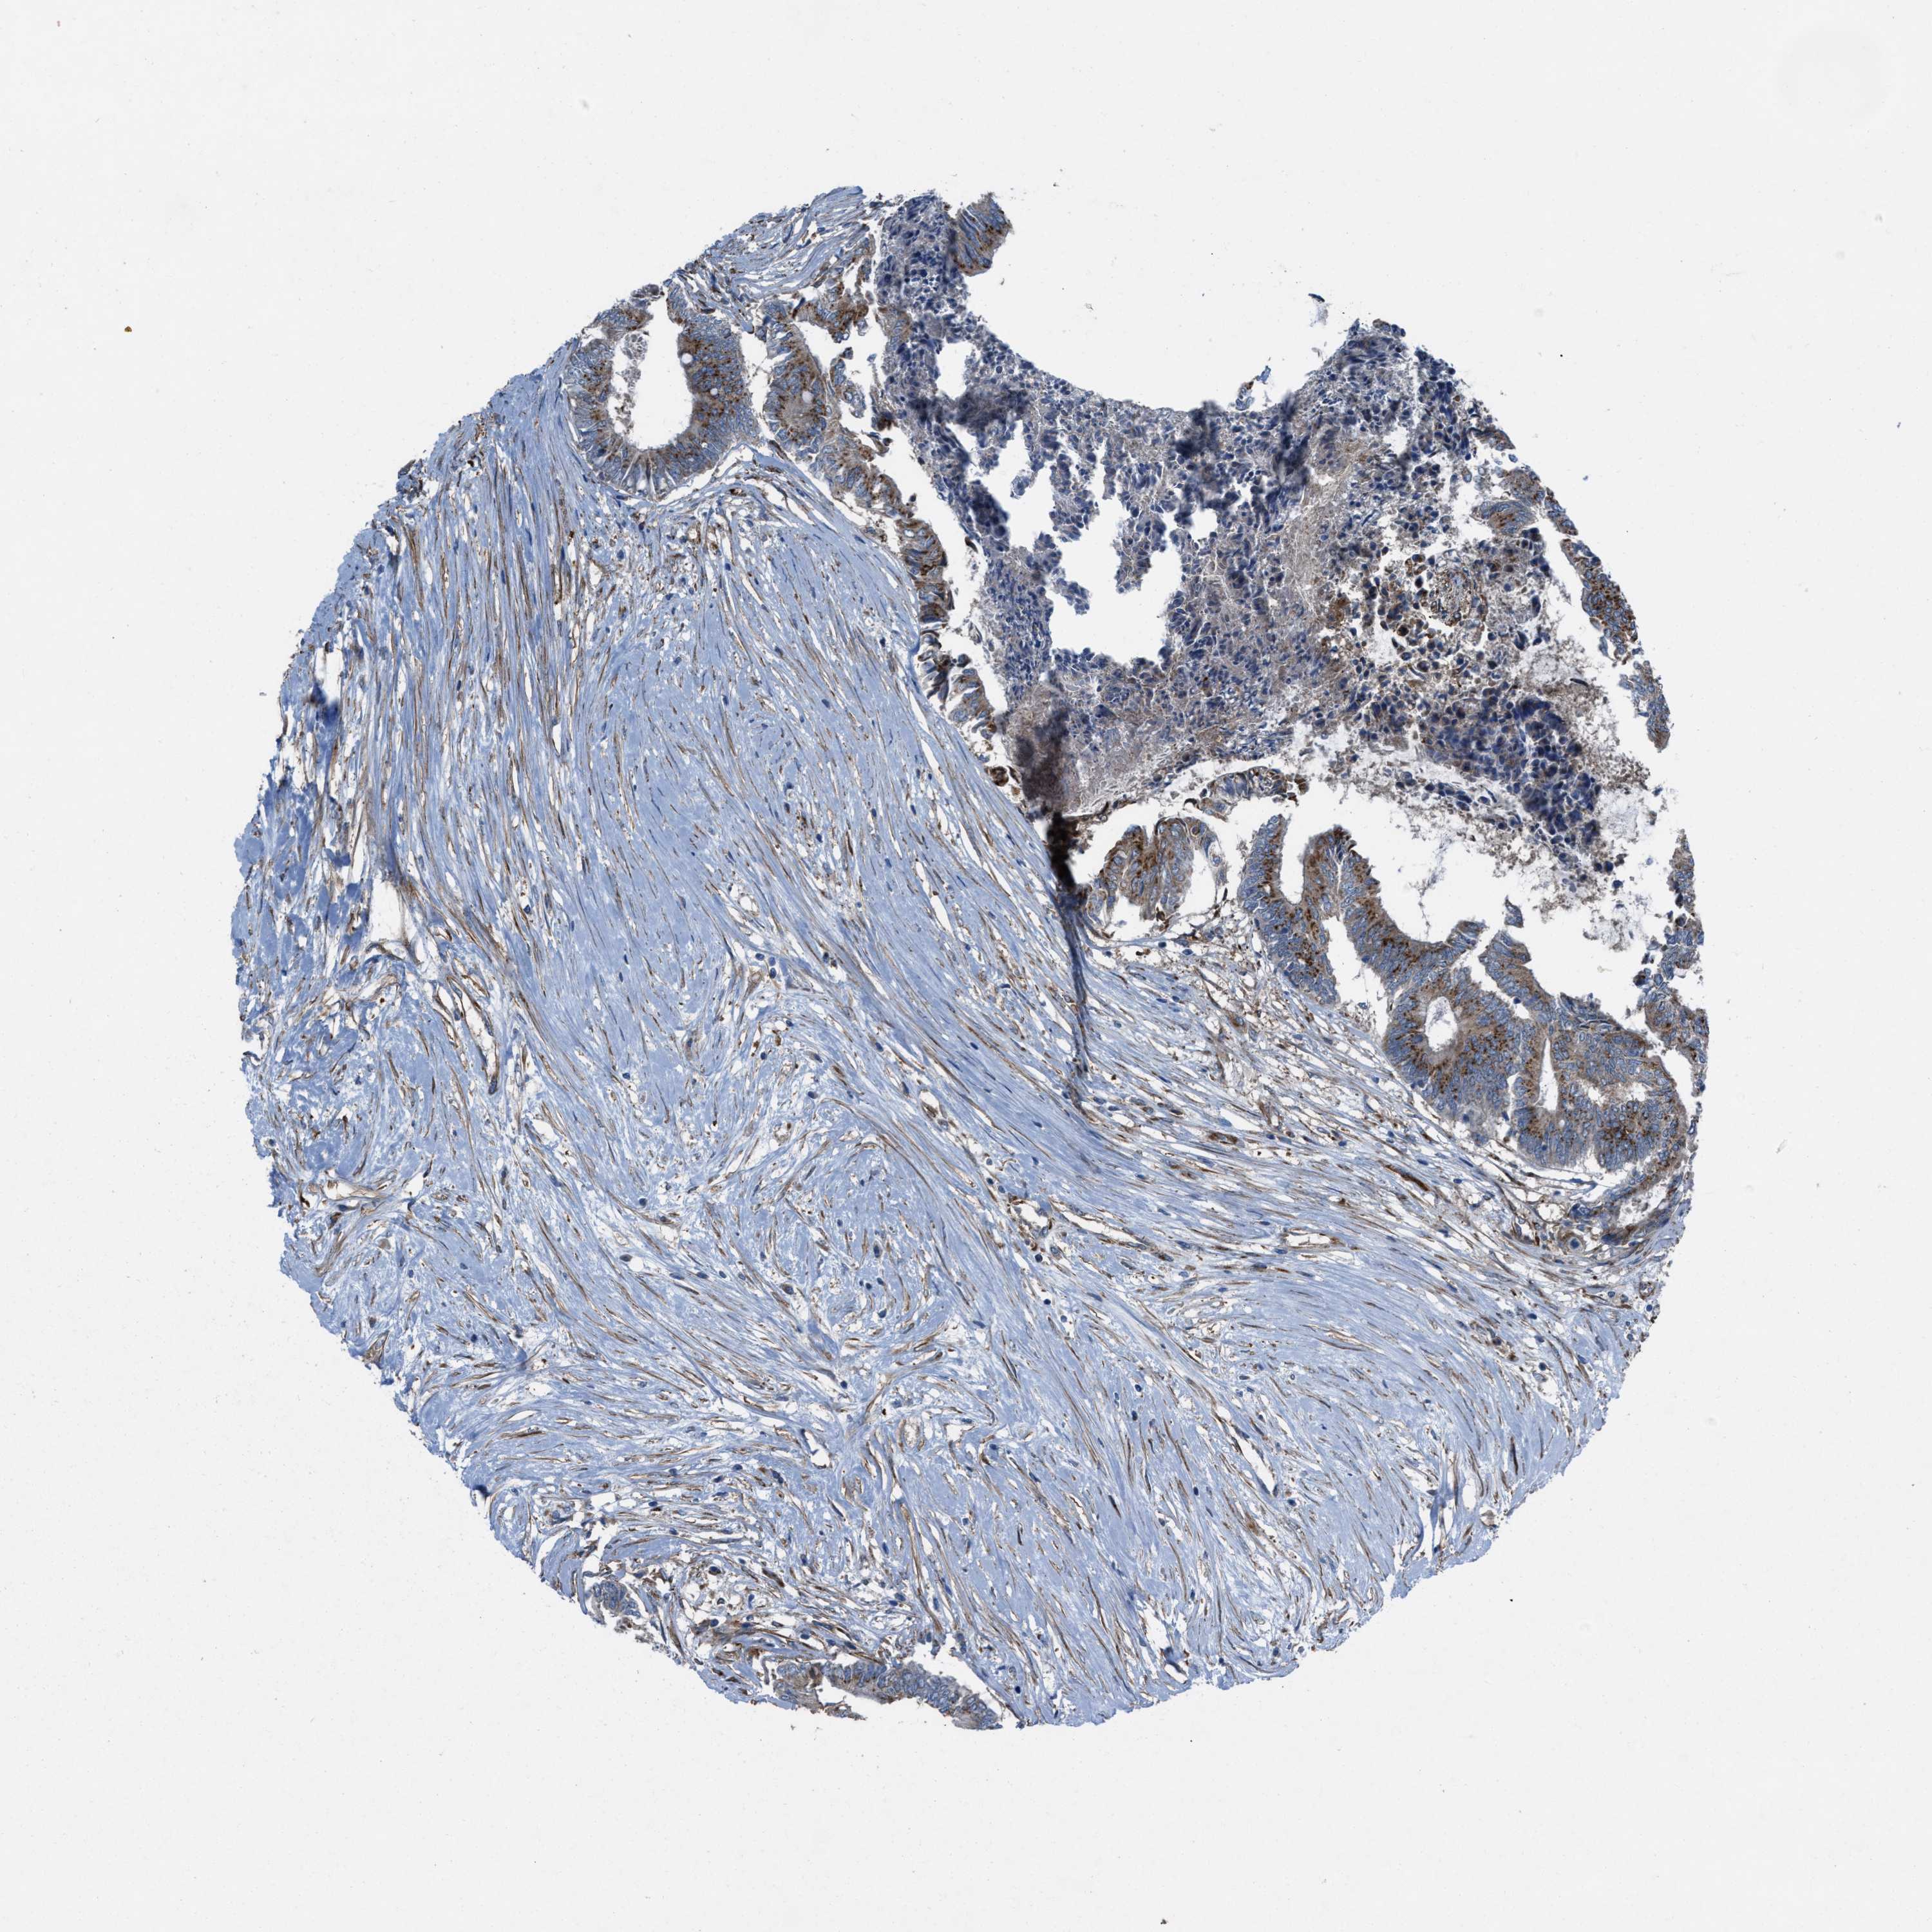

CANCER COLORECTAL CANCER Show tissue menu

Colorectal cancer

Human cancer

Colon adenocarcinoma